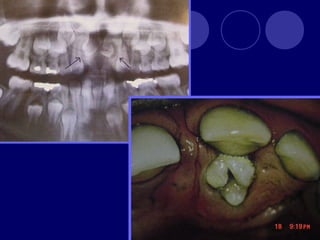

DENS IN DENTE

Diente invaginado, invaginación de las

células del epitelio interno del órgano del

esmalte.

Más frecuente en dientes anteriores

superiores, lateral, central,

2:1

Esmalte, dentina (cemento)

Radiográfico

 Etiología

 Fusión dental

 Invaginación activa

(campana)

 Retardo pasivo

 Desplazamiento

 Traumática o

infecciosa

 Clasifica en:

 Diente invaginado coronal

 Con forma coronaria normal

• Que no sobrepasa la corona

• Sobrepasa la corona y se alarga en raíz

• Invaginación radicular con fondo invaginado abierto

• Apertura lateral

 Forma coronaria anormal

 Diente invaginado radicular

DENS IN DENTE Dienteinvaginado, invaginación de las células del epitelio interno del órgano del esmalte. Más frecuente en dientes anteriores superiores, lateral, central, 2:1 Esmalte, dentina (cemento) Radiográfico

• 29.

 Etiología  Fusióndental  Invaginación activa (campana)  Retardo pasivo  Desplazamiento  Traumática o infecciosa

• 30.

 Clasifica en: Diente invaginado coronal  Con forma coronaria normal • Que no sobrepasa la corona • Sobrepasa la corona y se alarga en raíz • Invaginación radicular con fondo invaginado abierto • Apertura lateral  Forma coronaria anormal • Que no sobrepasa la corona • Sobrepasa la corona y se alarga en raíz • Invaginación radicular con fondo invaginado abierto • Apertura lateral  Diente invaginado radicular